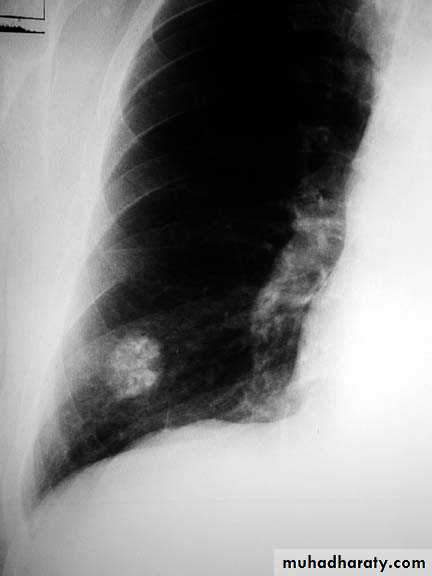

Tuberculoma mycetoma